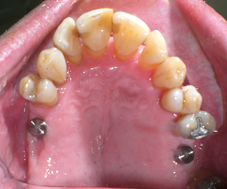

Arcade maxillaire avant traitement orthodontique, séquelles de maladie parodontale

Après traitement orthodontique et réalisation d’une attelle coulée collée (courtoisie Dr Patrick Fournier)